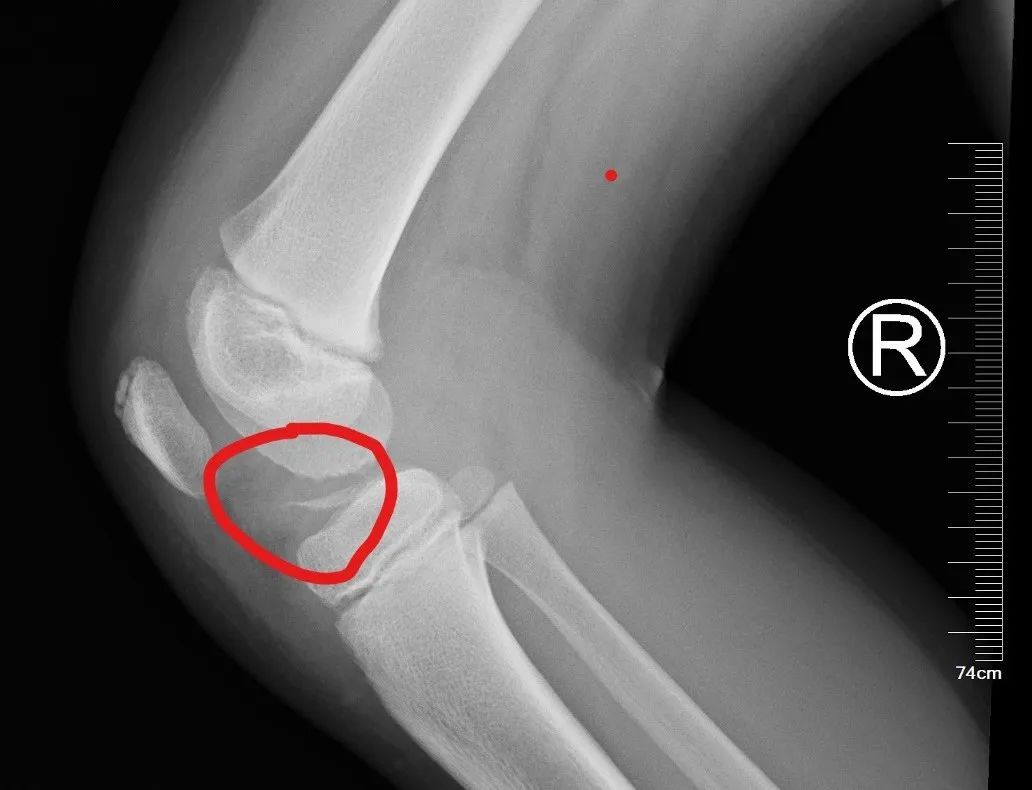

经过检查,接诊小儿骨科专家诊断患儿胫骨髁间嵴骨折!

胫骨髁间嵴骨折 好发于8-14岁的儿童,多为膝关节过伸损伤,如运动伤、摔伤,也可见于摩托车与自行车交通事故伤,大多数患儿负重行走困难。当发生胫骨髁间嵴骨折,膝关节会突然肿胀、疼痛,不能伸直和行走,应引起家长们的警惕。

此类骨折通常需手术治疗,否则极易造成膝关节不稳,甚至对患儿以后健康活动、运动生涯等会造成阻碍。